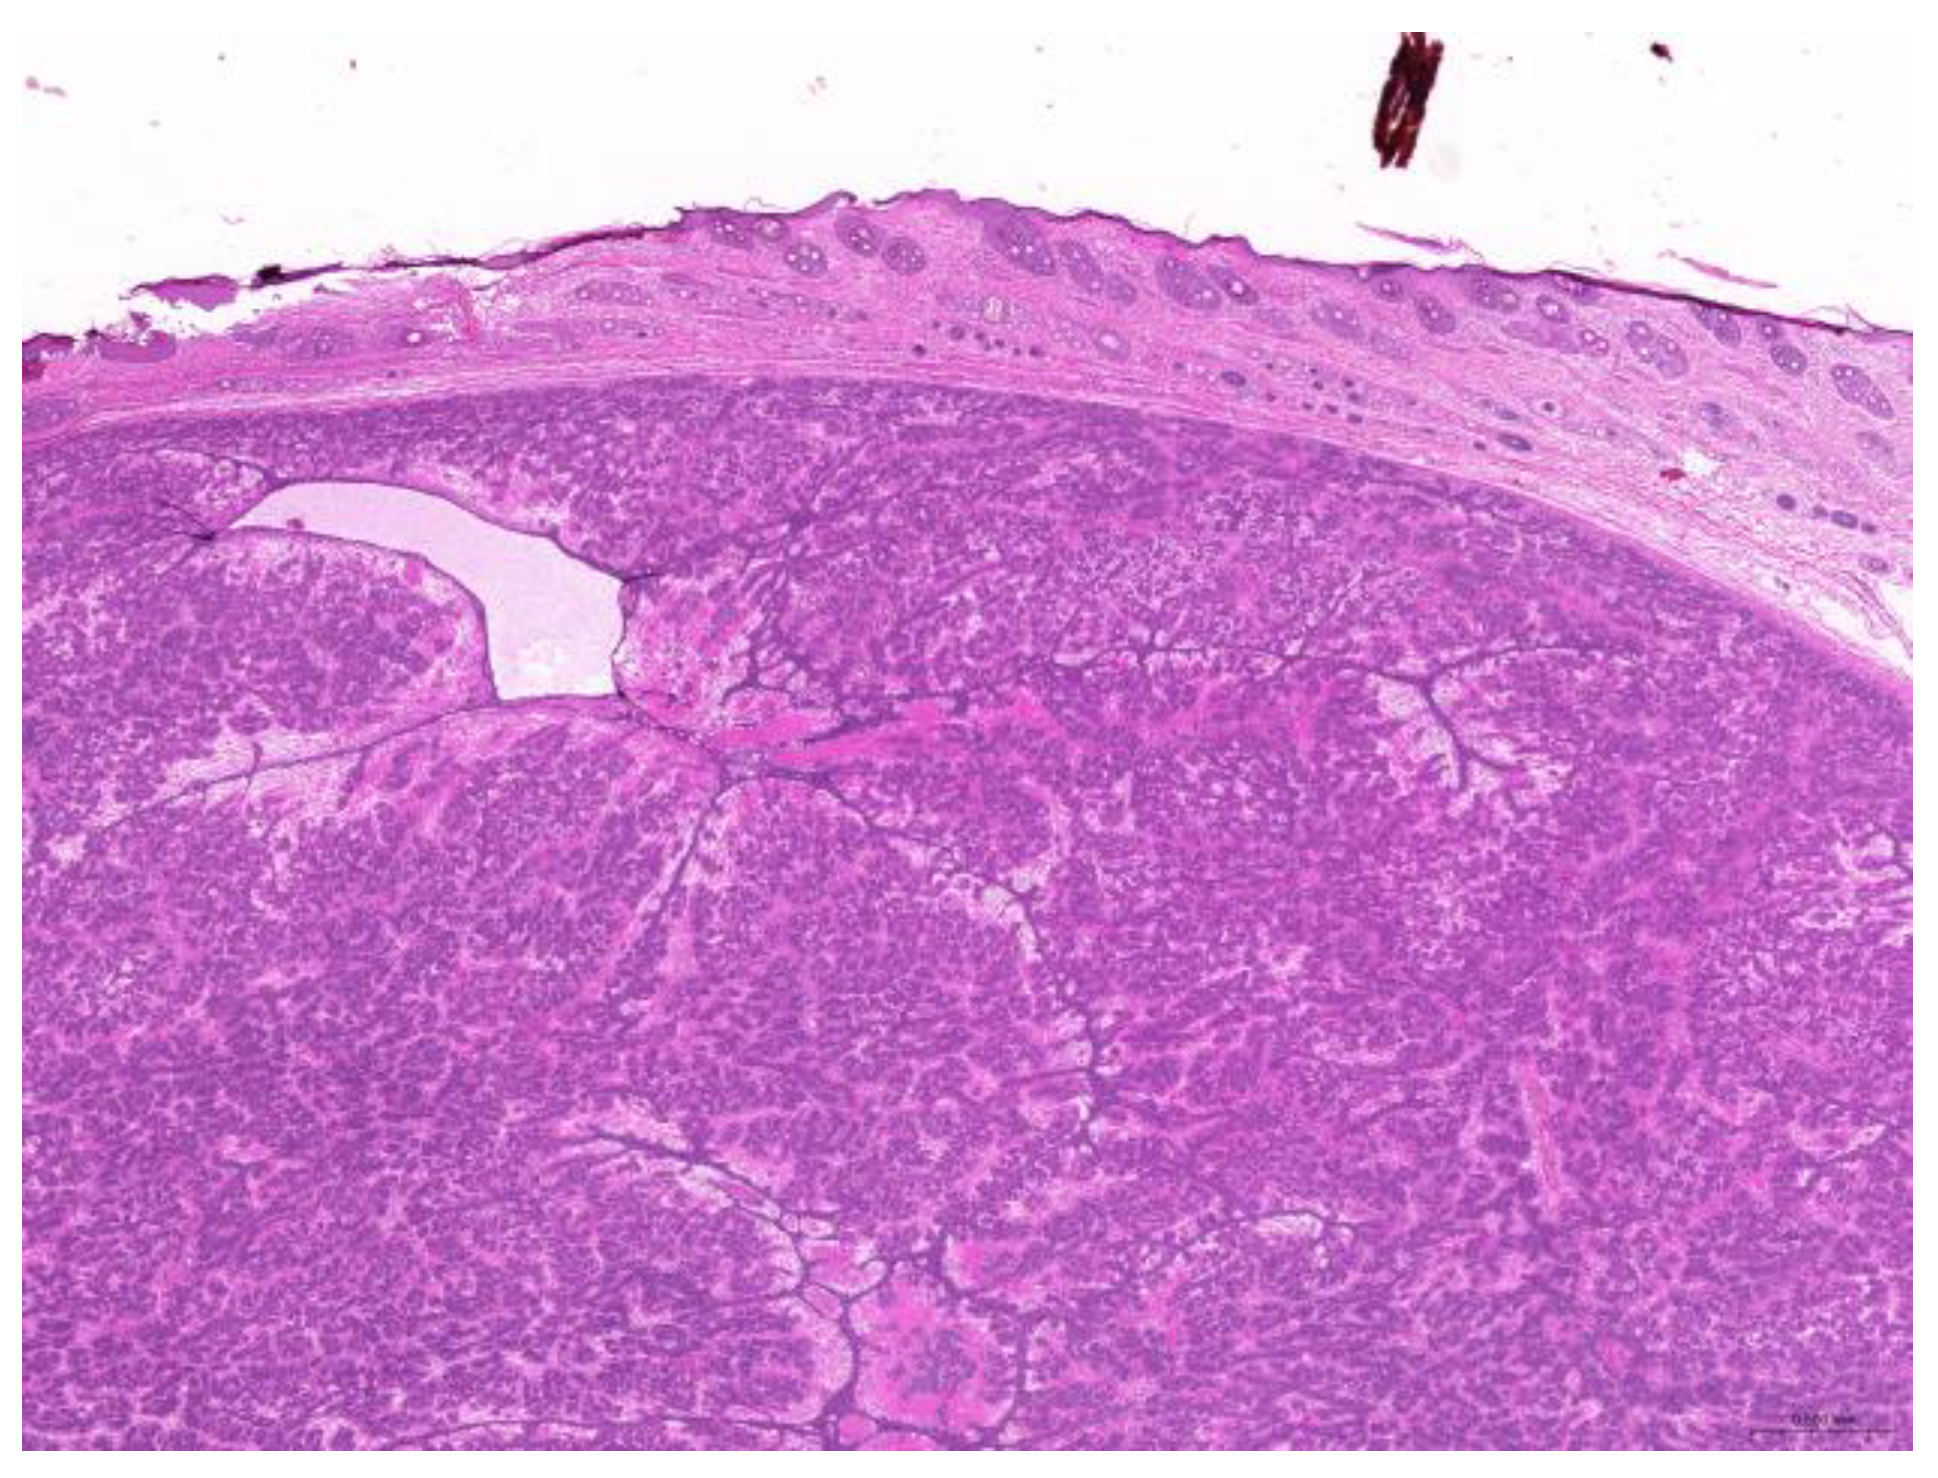

Thirty-six biopsy specimens were taken from the reproductive systems of 22 females and two males (a female-to-male ratio of 11:1). All of the females were intact, and 32 diagnoses were obtained from these 22 females. The median age of the affected females was 71 (20–132) months. The most common diagnoses were uterine adenocarcinoma (50%, 16/32) (Figure 6), followed by endometrial cystic hyperplasia (15.6%, 5/32), uterine adenomyosis (12.5%, 4/32), uterine leiomyoma (6.25%, 2/32), and luteoma (6.25%, 2/32). The median age of the females with uterine adenocarcinoma was 82 (42–132) months. From the two male rabbits, four diagnoses affecting the reproductive system were obtained. Both of these males were intact. The median age of the affected males was 113.5 (109–118) months. The most common diagnosis was interstitial cell tumor (50%, 2/4), followed by seminoma (25%, 1/4) and testicular atrophy (25%, 1/4).

Figure 6. Uterine adenocarcinoma. The neoplasm effaces the original uterine structure (scale bar = 500 µm). Hematoxylin and eosin staining.